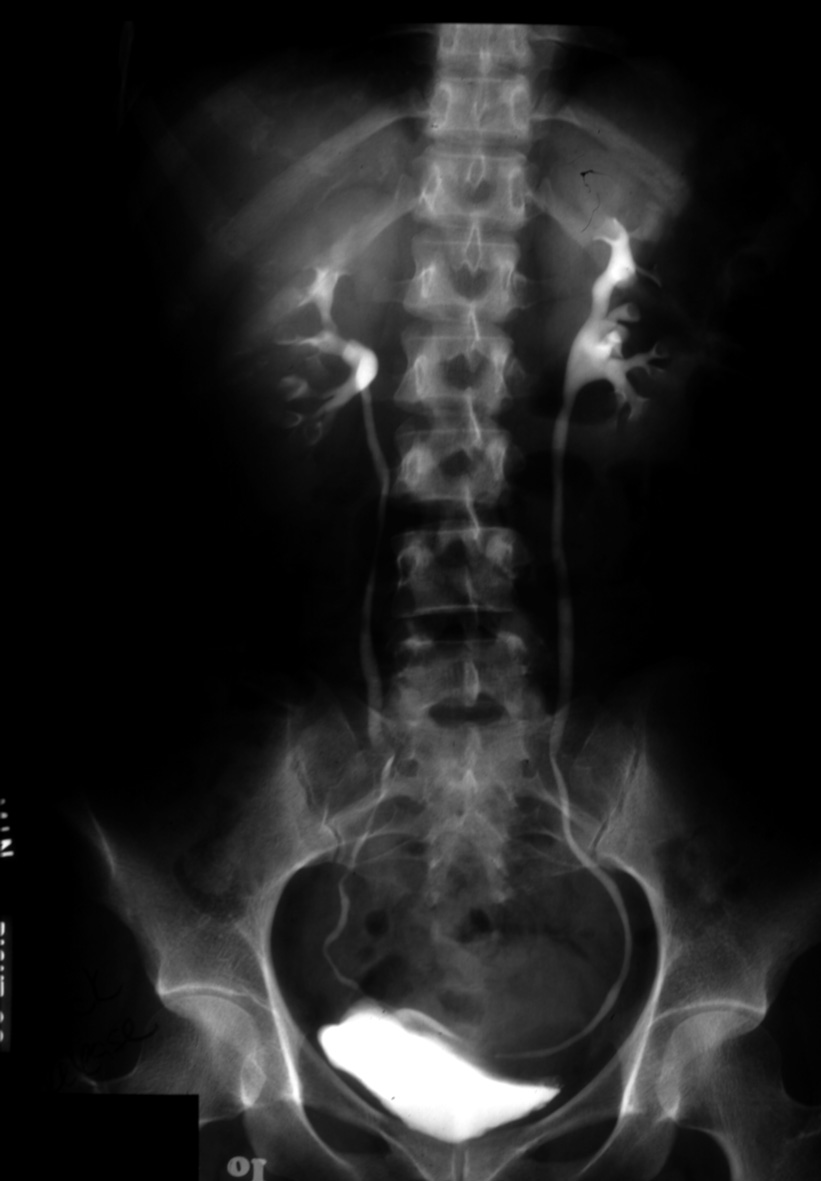

Normal Excretory Urogram (IVP)

Identify: renal contour, calyces, renal pelvis, ureter, bladder